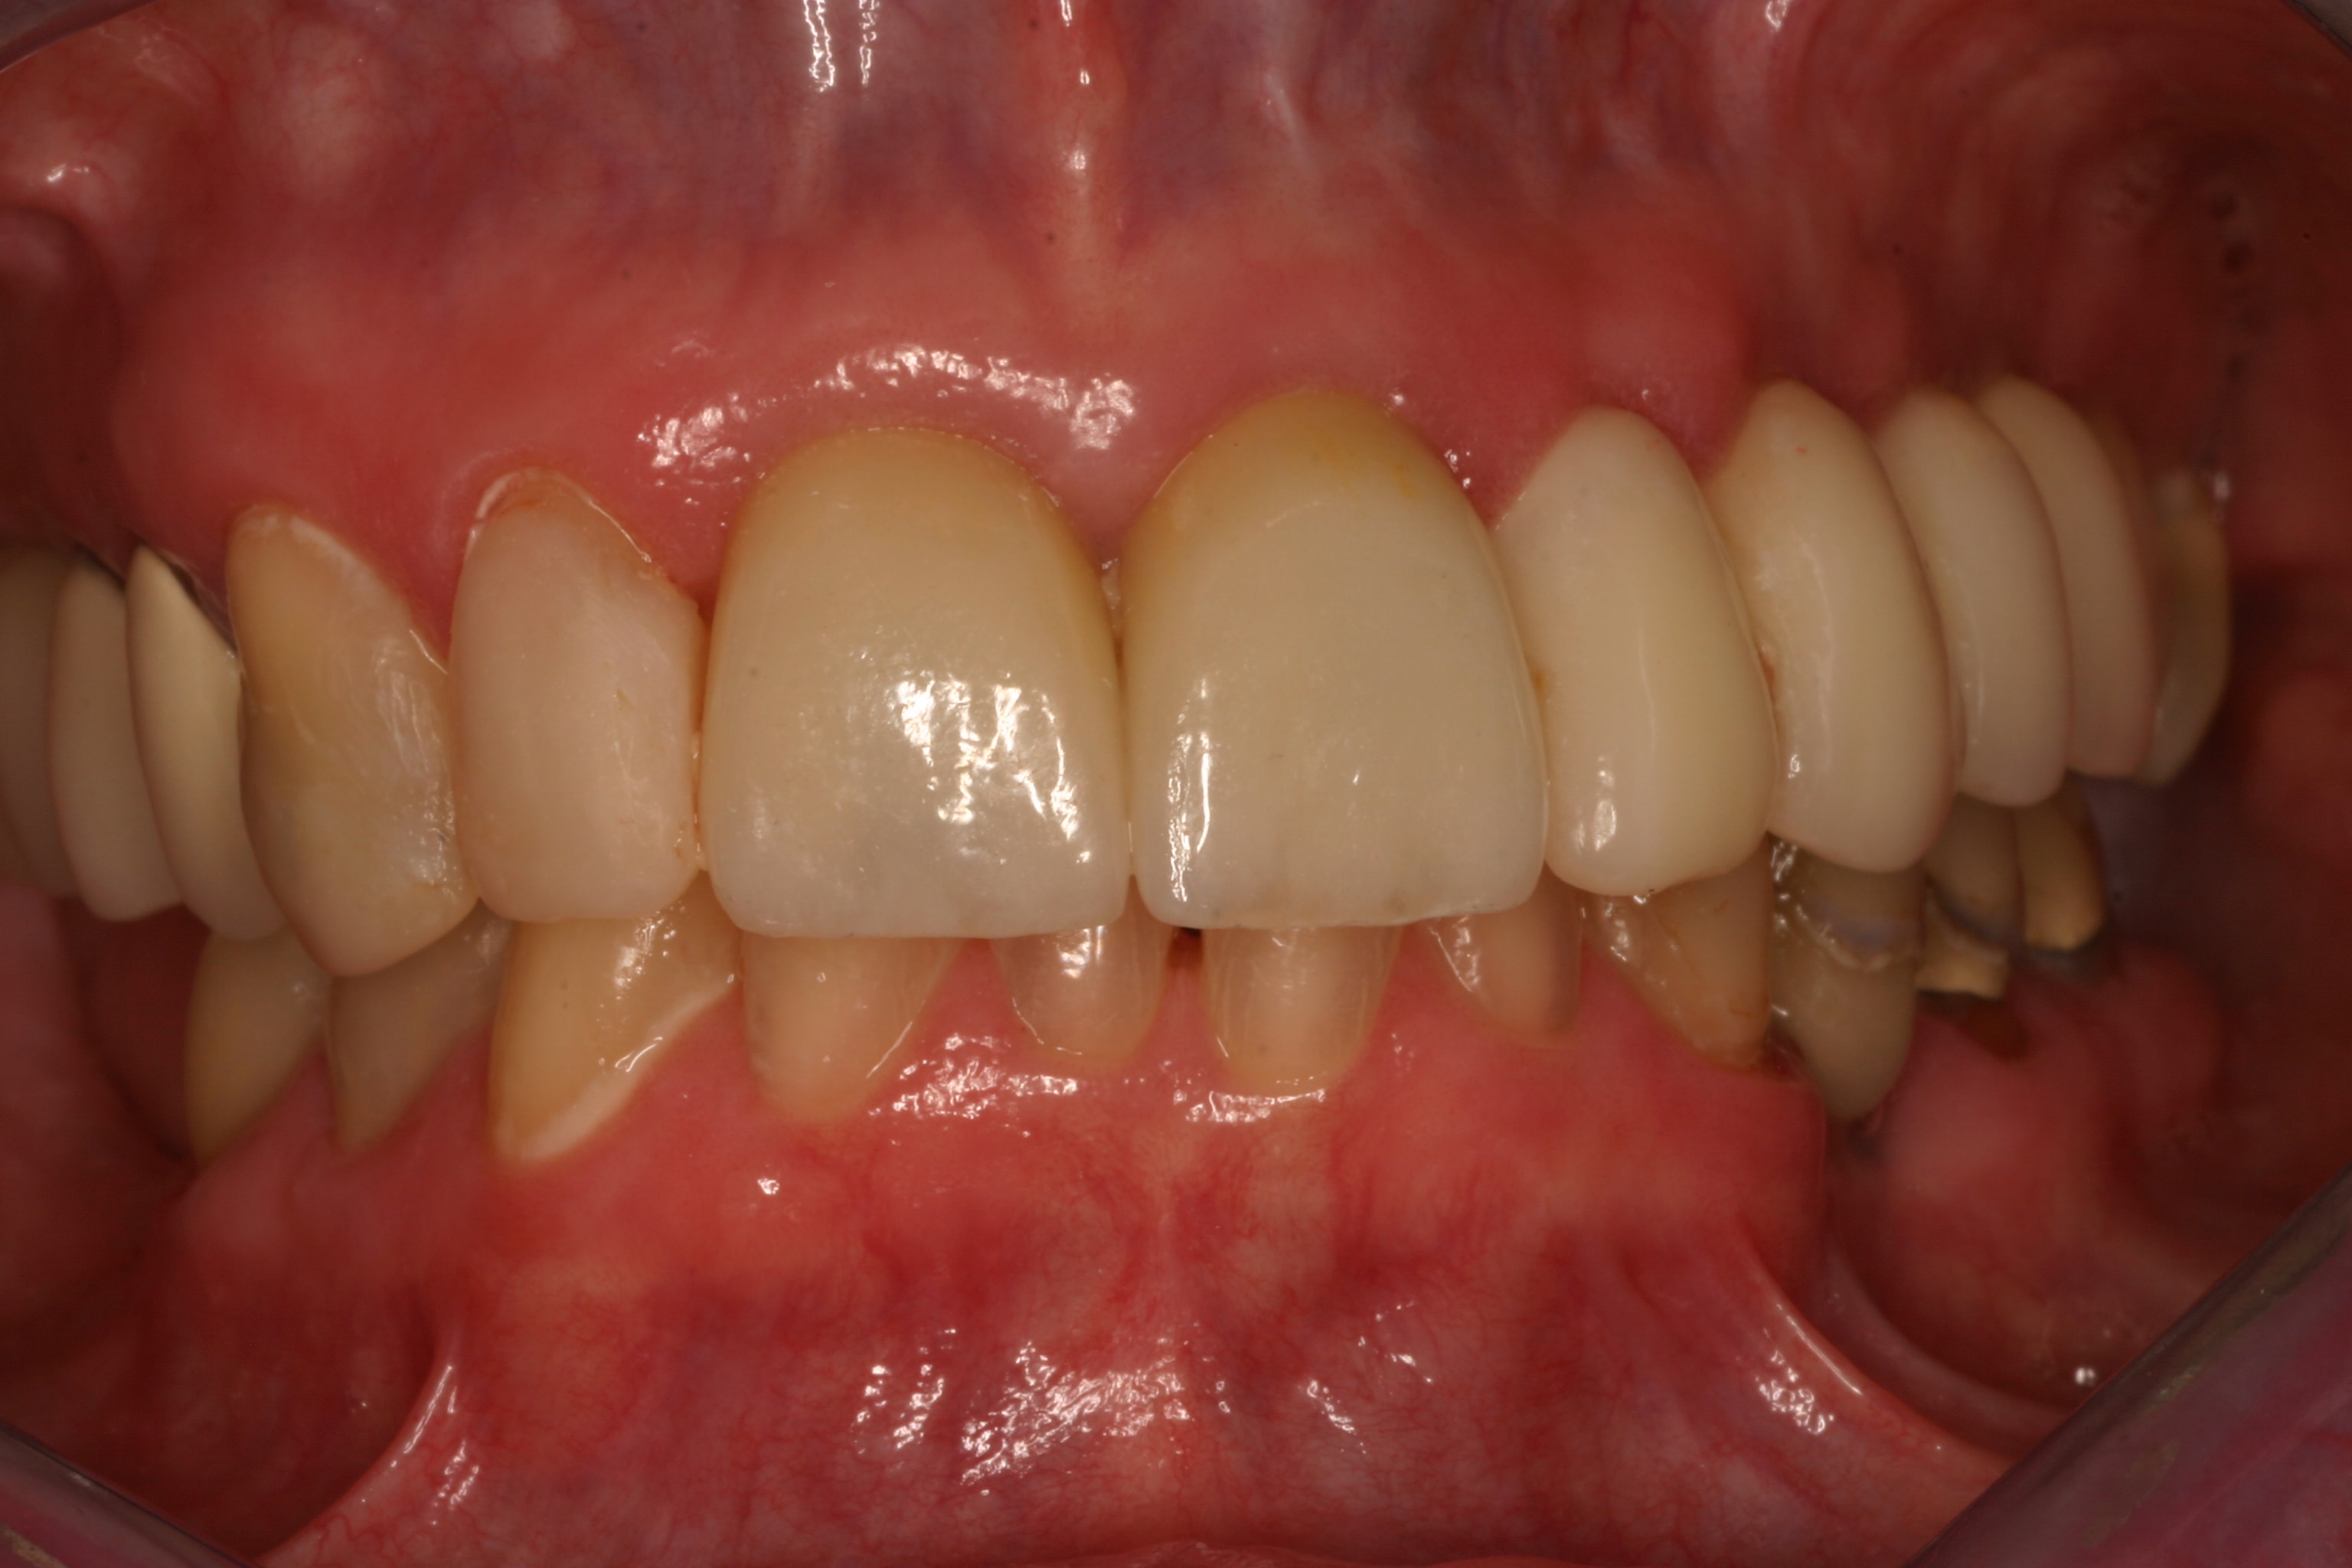

She had preexisting PFM restorations on teeth Nos. 8 and 9 (Figure 19), both of which had been endodontically treated (Figure 20). In August 2011 the crown on No. 8 dislodged and was recemented on an emergency basis; in November 2011 both crowns (Nos. 8 and 9) dislodged, and both teeth were given a questionable prognosis.

The final impression (closed tray) was obtained in April 2012. The final ceramic crowns (IPS e.max Ceram) and custom porcelain-veneered, regular-diameter (RD) UCLA abutments (Genesis; and Creation CC, Jensen Dental, www.jensendental.com) (Figure 24, shown with PFM crowns and retention screws) were delivered in May 2012. Using a platform-switched connection, the abutments were torqued to 30 Ncm, the access holes sealed with Teflon, and the final crowns cemented with RelyX Unicem. Figure 25 through Figure 28 show the final IPS e.max Ceram crowns from periapical, facial, and incisal views, with a midfacial PD of 3 mm at the 18-month follow-up (Visit 7). A thick biotype is evident in Figure 26, as determined by the inability to detect the outline of the periodontal probe inserted below the restoration’s gingival margin.50 This image also demonstrates an excellent esthetic outcome.

After this visit, additional restorative work was completed on teeth Nos. 6 and 7. Figure 29 and Figure 30 (retracted and smile views, respectively, at 3 years, Visit 8) show the excellent esthetic outcome registered during the 3-year postoperative period.